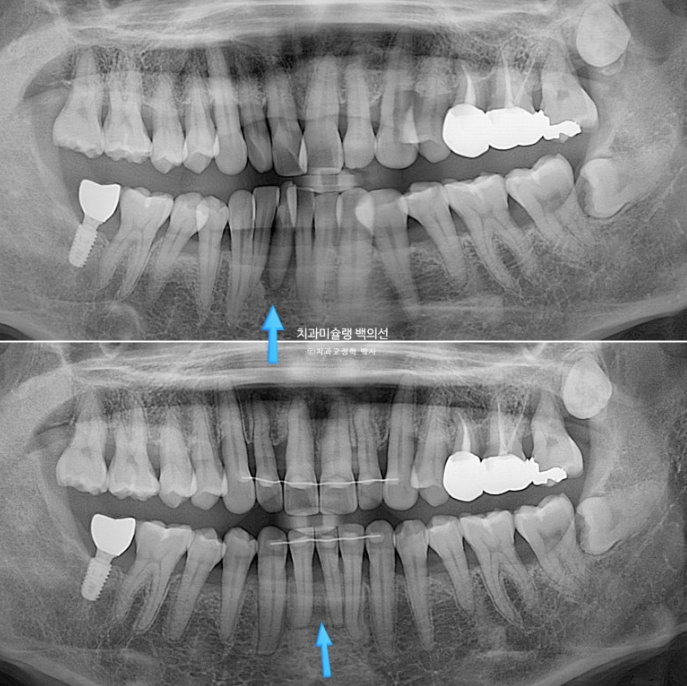

파란 화살표 치아는 잇몸이 검붉게 보입니다.

엑스레이상 이미 치주염이 상당히 진행이 되어 발치가 불가피한 상황이였습니다.

파란 화살표 치아가 치주염이 심해 발치한 치아입니다.

1년간의 교정치료 기간 동안 잇몸뼈는 잘 유지가 되었고 치근평행도는 양호합니다.

개인적으로 안 보이는 부분까지 완벽을 기하기 위해서 치근평행도에 집착하는 편입니다만 아래 앞니 뿌리가 완벽히 평행하지 못한 부분이 조금 아쉽습니다.

파란화살표가 발치한 치아 자리이고 이미 심한 치주염으로 골손실이 심해 인접치아 뿌리가 해당 부위로 충분히 이동해주지 못하기 때문입니다.

뼈가 튼튼해야 그쪽으로 치아이동이 잘 됩니다. 반대로 뼈가 없는 부위로 치아가 이동하진 못합니다.